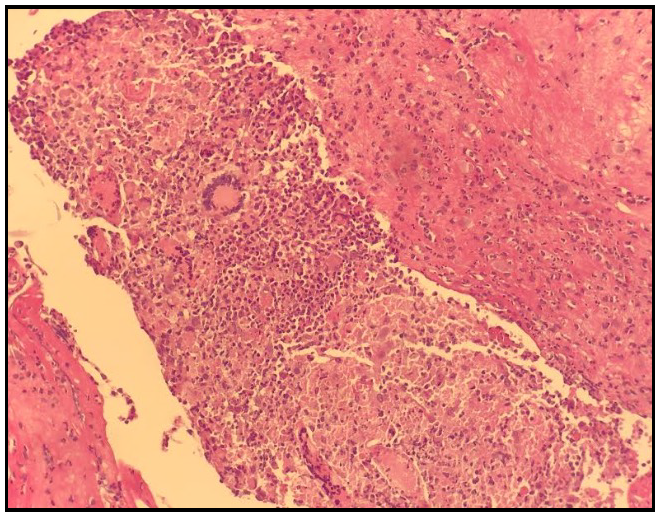

Faced with unfavorable evolution under empirical antibiotic therapy, we decided to withdraw the PD catheter on D+10, with biopsy of the peritoneum, the anatomic pathological examination of which showed a peritoneal coating altered by a granulomatous inflammatory infiltrate made up of epithelioid cells and giant cells with the presence of caseous necrosis (Figure 1andFigure 2).

Figure 1.Biopsy of the peritoneum showing two granulomas with giant cells.

Figure 2.Biopsy of the peritoneum showing a giant cell granuloma with caseous necrosis.